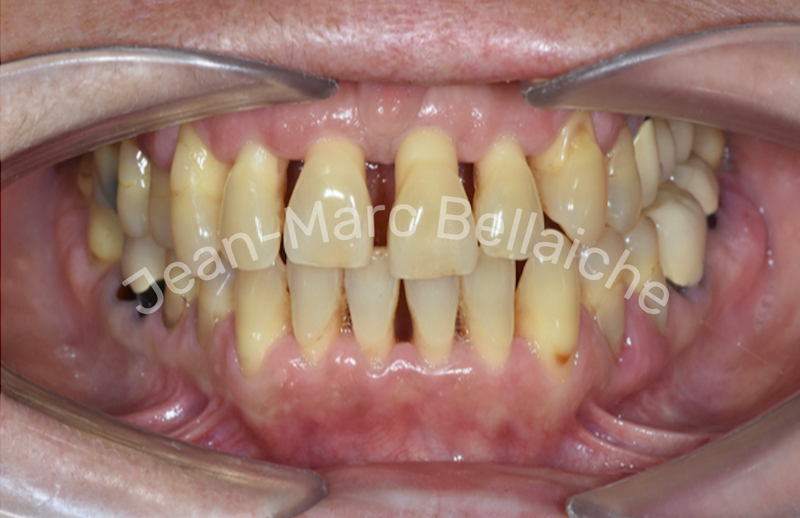

Cas 5 : Traitement orthodontique et esthétique – Cas parodontal

Situation "Avant Traitement" : Espaces entre les dents, dénivellation des hauteurs dentaires et parodontite.

Chez cette patiente adulte, l’objectif était de refermer les espaces, d’harmoniser le sourire et de compenser une perte osseuse liée à une maladie parodontale. Après stabilisation de la parodontite, le traitement orthodontique a été mené avec gouttières transparentes à forces douces, respectueuses du support osseux. Il a été complété par un blanchiment dentaire et un remodelage esthétique pour redonner au sourire équilibre et naturel.